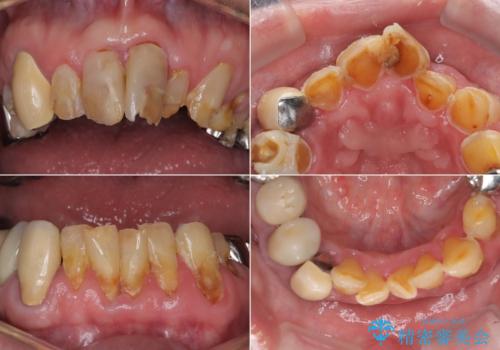

- 強い酸によって歯が広範囲にわたって侵食され、「歯がボロボロになった」と主訴に来院されました。詳細な診査の結果、重度の酸蝕症と診断。失われた歯質や咬み合わせの崩壊が著しいことから、単一の治療では対応が困難と判断し、矯正治療、インプラント治療、セラミック治療を組み合わせた総合的な治療計画を立案しました。矯正治療後に最終的にセラミックを用いて機能性と審美性を回復。患者様と綿密な話し合いを重ね、長期的な口腔内の健康維持を見据えた最適な治療を行いました。

酸蝕症の原因に関しては、医科のほうで解決済みでしたので、失われた機能、審美性の回復のため矯正治療によって歯並びと咬み合わせのバランスを整えセラミックによる修復を行ました。

保存できないと判断した歯は抜歯しインプラントにて治療をおこなっています。